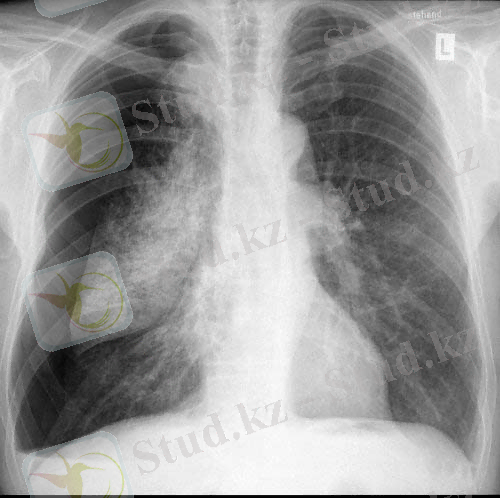

Пневмоторакстың рентгенологиялық белгілері-

- Тері астылық эмфизема- қорытынды рентгенограммада «қабатталған қамыр» түрінде көрінеді (сурет 6), толық тері асты эмфиземасында қабырғалар құрылымы, өкпе тіні нашар жіктеледі, үлкен кеуде бұлшықеті бойымен радиальді «сәулелер» анықталады (сурет 7) .

- өкпеліе суреттің жоғалуымен «ағару» аймақтары (сурет 8)

- өкпе шеті анықталады (сурет 8) .

Сурет 6. Кеуде қуысының қорытынды рентгенограммасында пневмоторакс кезіндегі тері асты эмфиземасы.

Сурет 8. Пневмоторакс кезінде қорытынды рентгенограмма:

Сызықтармен өкпе суреті және өкпе шеті жойылған «ағарған» бөліктері көрсетілген.